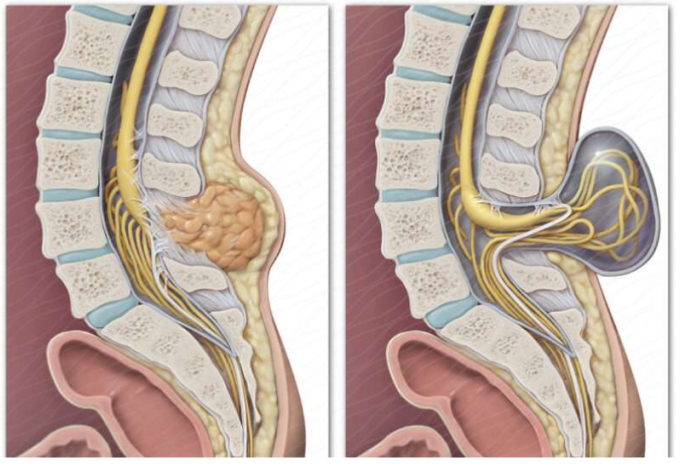

北京清华长庚医院2月28日电(神经外科 孙振兴) 定义:简单来说,脊髓拴系是一种先天性的神经管畸形,正常情况下,脊髓在脊柱的椎管内可以自由地上下浮动。但在脊髓拴系患者中,脊髓的末端(圆锥)被某些异常的组织结构(如脂肪瘤、纤维束带、紧绷的终丝等)固定、拉扯住了,导致脊髓像一根被拴住的橡皮筋,张力增高,无法正常活动,就像被缰绳拴系的野马。这种持续的牵拉会干扰脊髓的血液供应和神经功能,随着孩子的成长(如弯腰、长高)或日常活动,损伤会逐渐加重。若出现大小便障碍、下肢疼痛无力和畸形等一系列症状,称为脊髓拴系综合征。

正常脊髓末端在腰1-2拴系脊髓末端在腰2以下 拴---系

脊髓拴系合并脂肪瘤 脊髓拴系合并脊膜脊髓膨出